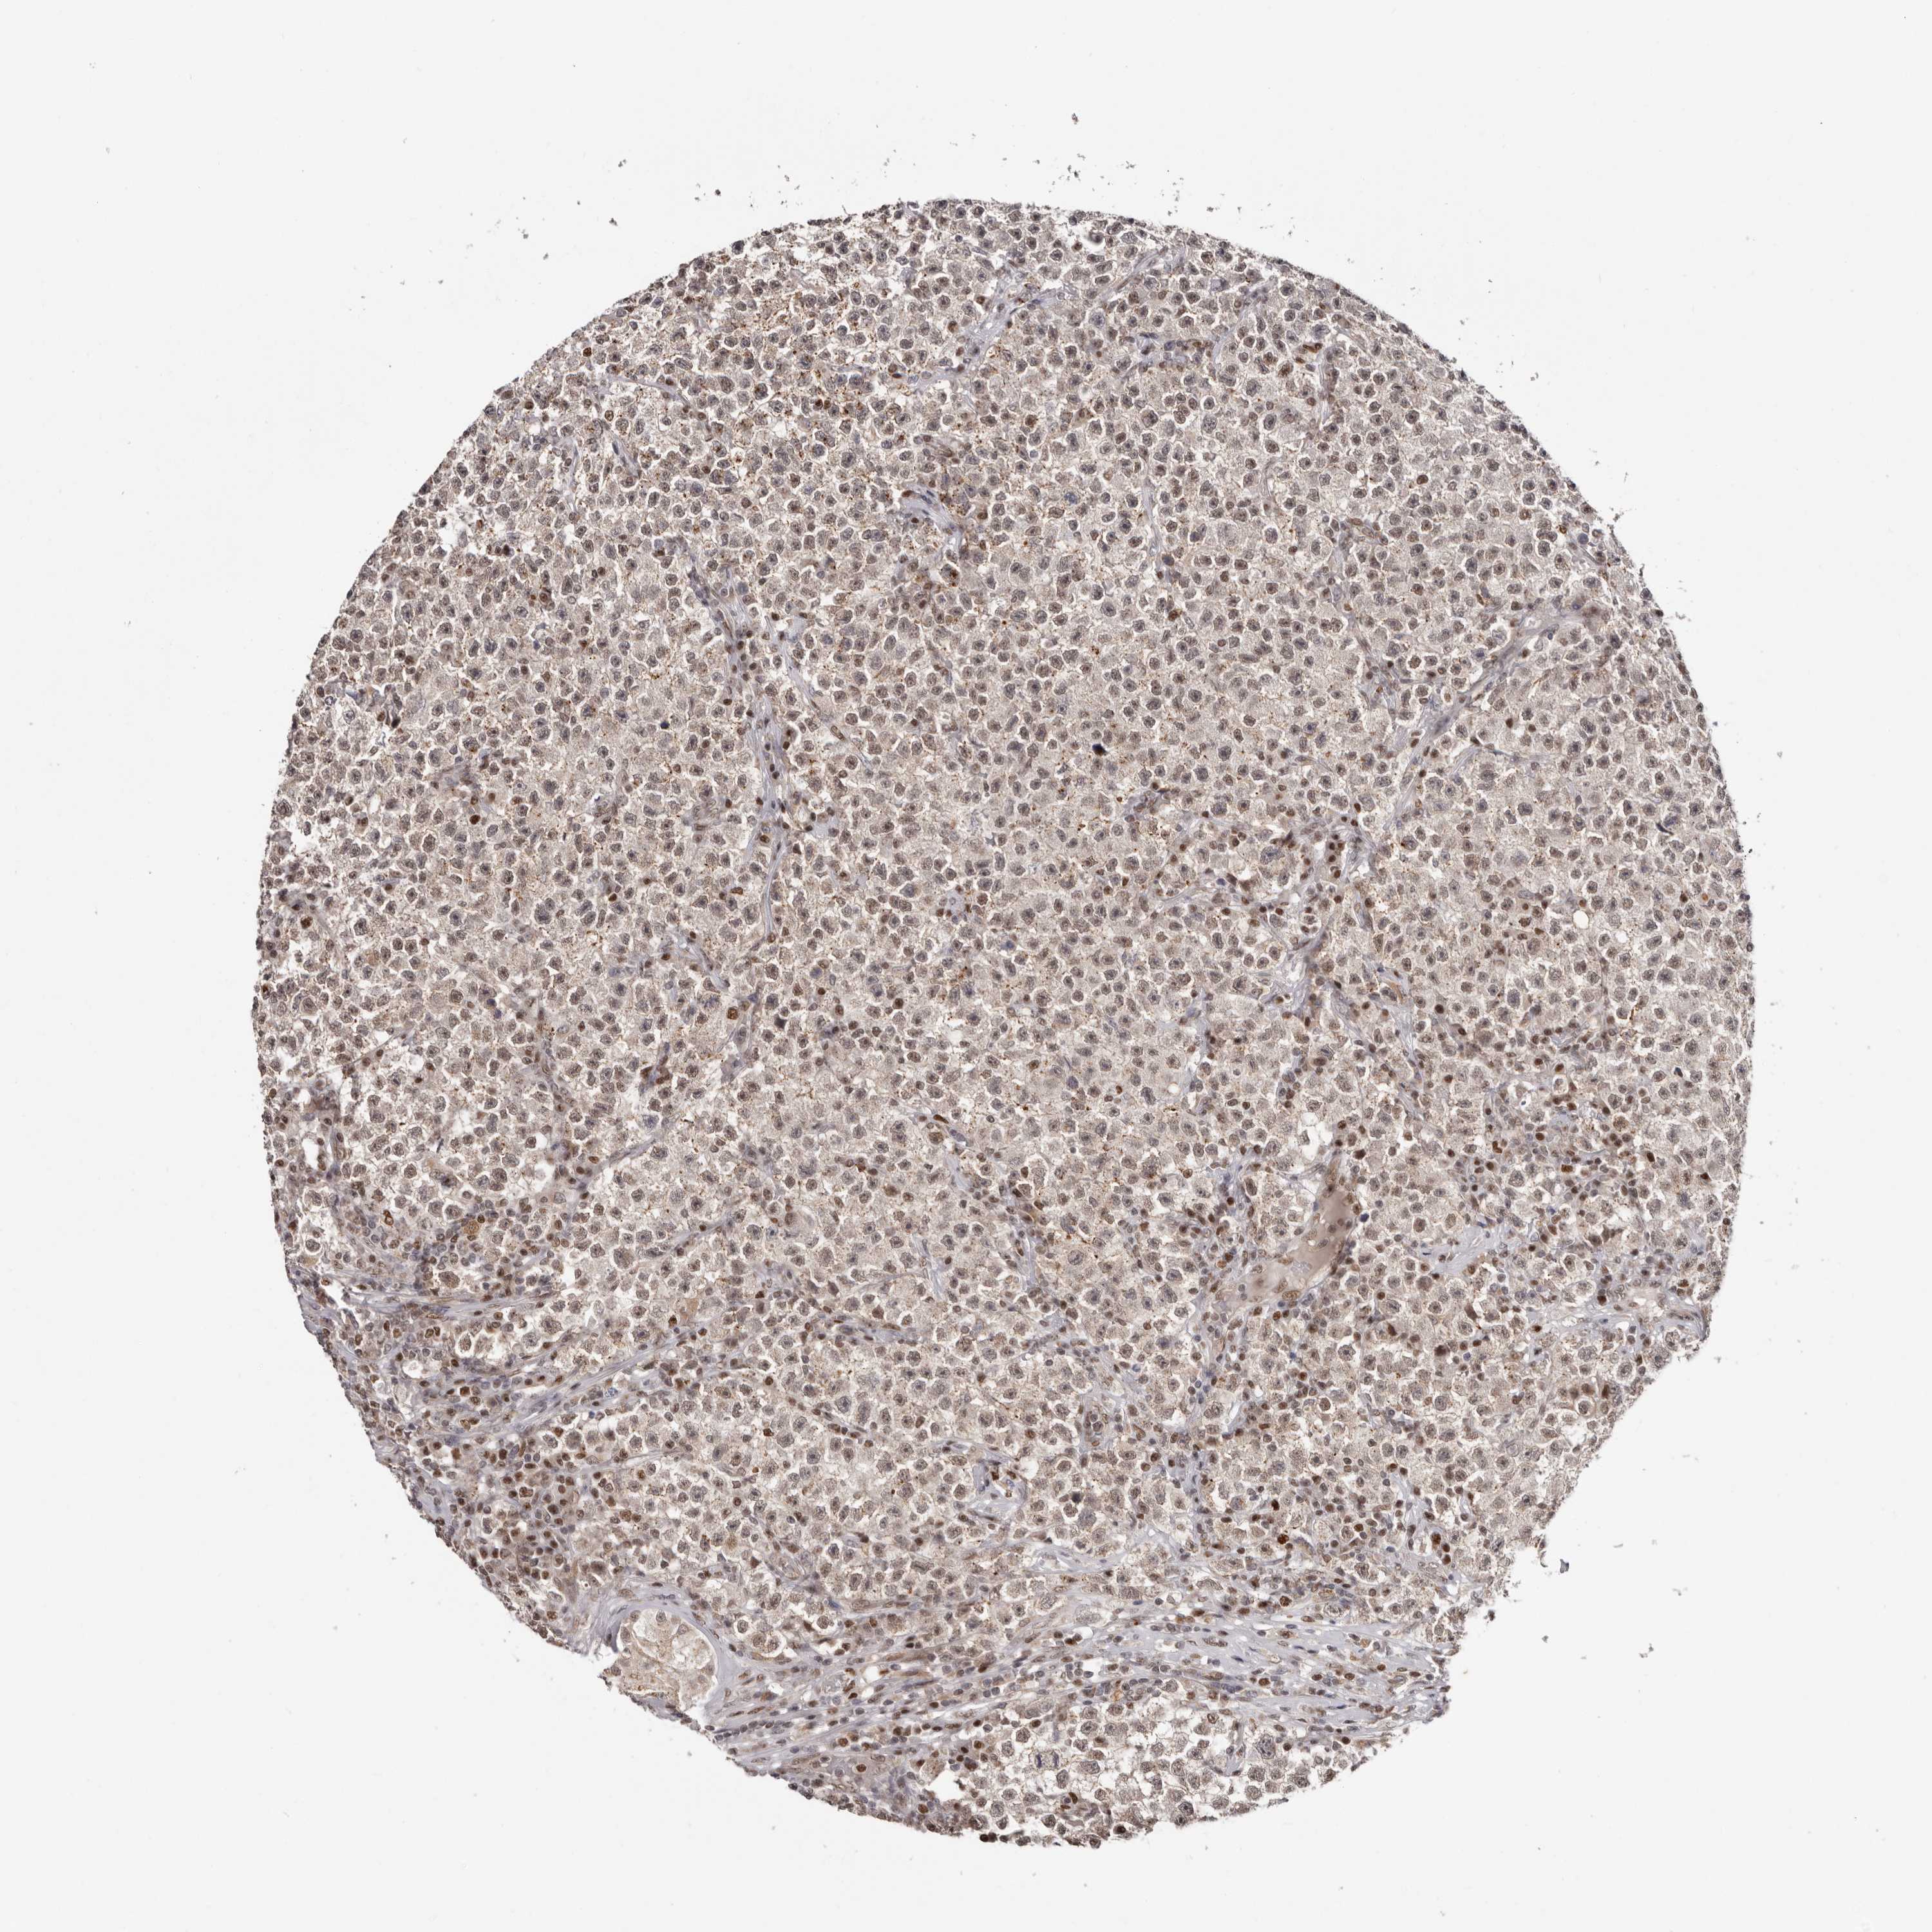

TESTIS CANCER - Protein expressioni

A mouse-over function shows sample information and annotation data. Click on an image to view it in a full screen mode. Samples can be filtered based on level of antibody staining by selecting one or several of the following categories: high, medium, low and not detected. The assay and annotation is described here.

Note that samples used for immunohistochemistry by the Human Protein Atlas do not correspond to samples in the TCGA dataset.

Antibody stainingi

Antibody staining in the annotated cell types in the current human tissue is reported as not detected, low, medium, or high, based on conventional immunohistochemistry profiling in selected tissues. This score is based on the combination of the staining intensity and fraction of stained cells.

Each image is clickable and will lead to virtual microscopy that enables deeper exploration of all samples and also displays staining intensity scores, fraction scores and subcellular localization as well as patient and tissue information for each sample.

Antibody CAB026212

Seminoma, NOS